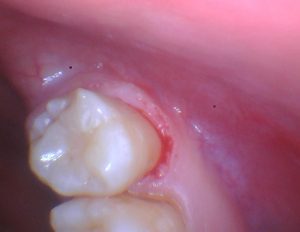

The teeth were prepared, etched, bonded, and restored with ACTIVA. The flowable characteristics of ACTIVA allowed me to complete each posterior restoration in eight minutes. The material adapted easily to the tooth, produced no bubbles or voids, and provided excellent results.